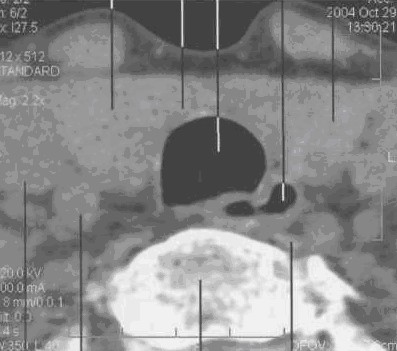

Компьютерная томография ЩЖ

КТ железы проводится от яремной вырезки до уровня Су. Толщина среза -- 8 мм, шаг -- 4--8 мм. Обычное положение неизмененной железы -- на 2 см выше верхнего края гру­дины.

Форма -- в виде двух овалов с относительно ровными контурами, хорошо отграниченными от окружающих тканей.

Поперечные размеры составляют 30x20 мм, высота -- 30--40 мм.

Структура -- однородная. Денситометрическая плотность (при содержании в паренхиме железы 0,65 мг/г йода) -- 70+10 HU.

Кпереди от железы визуализируются грудино-щитовидные и грудино-подъязычные мыш­цы, по передней поверхности которых проходят наружные яремные вены.

Латеральной поверхностью железа прилежит к внутренней яремной вене и сонной арте­рии. Слева сонная артерия лежит под веной, справа проходит ближе к телу позвонка по задне-латеральной поверхности железы.

По заднемедиальному краю щитовидной железы, кзади от трахеи располагаются паращитовидные железы, которые могут быть видны у тучных пациентов. Паращитовидные желе­зы могут визуализироваться между собственной капсулой железы и жировой клетчаткой. Число паращитовидных желез колеблется от 2--4 до 5--6. Их длина составляет 5--6 мм, толщина -- около 4 мм.

Задний край щитовидной железы отделен от тел пятого и шестого шейных позвонков длин­ной мышцей шеи. В центре среза между трахеей и серединой тел позвонков располагается пи­щевод (рис. 28)

Рис. 28. Серия КТ изображений щитовидной железы на разных уровнях щитовидного хряща в аксиальной плоскости.